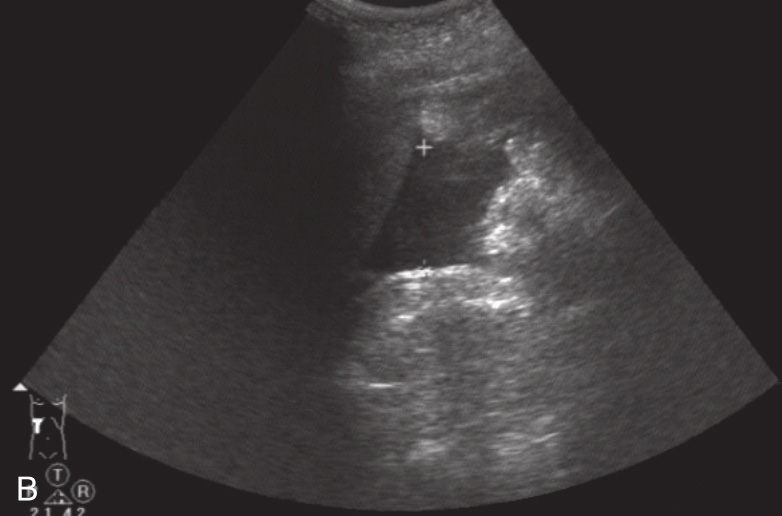

图1-12-1 真性肝破裂灰阶超声图像

A.肝右叶近被膜处片状低回声区;B.肝下积液